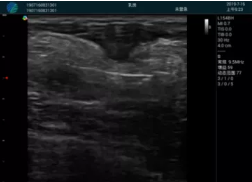

清晰顯示孕囊,通過軟件包計算孕齡7w+6d

M20實(shí)時引導(dǎo),術(shù)中清晰顯示孕囊被破壞和抽吸針的過程,清晰顯示吸引針

抽吸結(jié)束后縱切子宮,孕囊已被完全抽吸,未見明顯殘留

橫切子宮,發(fā)現(xiàn)右側(cè)宮腔靠近宮角處有少許脫模樣殘留

M20引導(dǎo)下,抽吸針找到右側(cè)宮角處再次清掃

二次抽吸后再次進(jìn)行超聲檢查,宮腔未見殘留,宮腔線清晰顯示